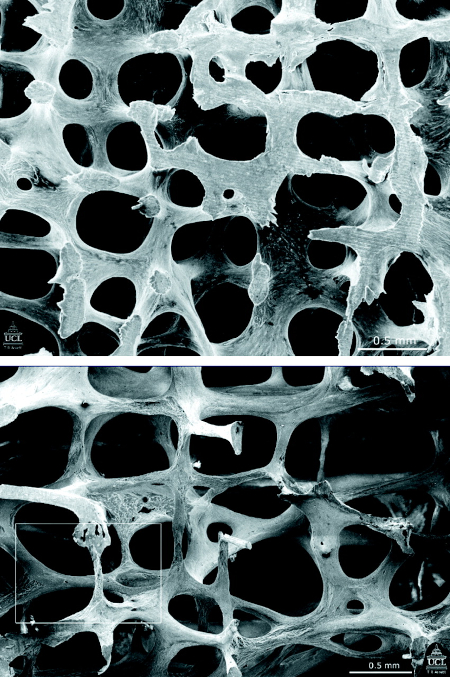

Micrografías electrónicas de barrido que muestran la estructura de la vértebra L3 en una mujer de 31 años (arriba) y en una mujer de 70 años (abajo). Tenga en cuenta que muchas de las estructuras en forma de placa se han convertido en varillas delgadas

Poole KES, et al. BMJ 2006; 333: 1251; Usado con permiso